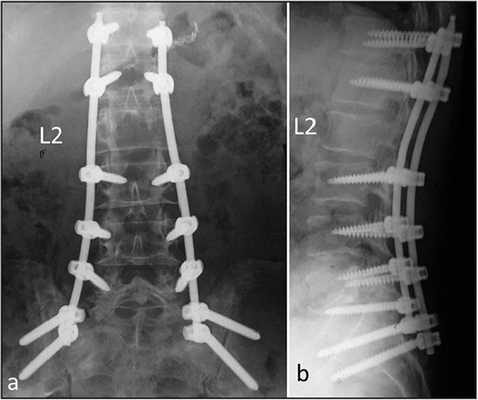

Транспедикулярная фиксация системой expedium

Стабилизация поясничного отдела.

Коррекция кифоза грудного отдела.